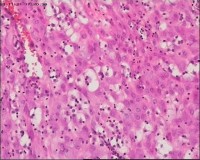

性别

女

年龄

20岁

临床诊断

一般病史

停经3月,阴道不规则流血7天。

标本名称

宫刮物

大体所见

灰白灰红碎组织一堆,大小为7*6*1cm,部分组织呈水泡状

水肿的绒毛和蜕膜,没看到增生的滋养细胞。必要时可做IHC除外部分葡萄胎,并结合临床HCG。

考虑葡萄胎